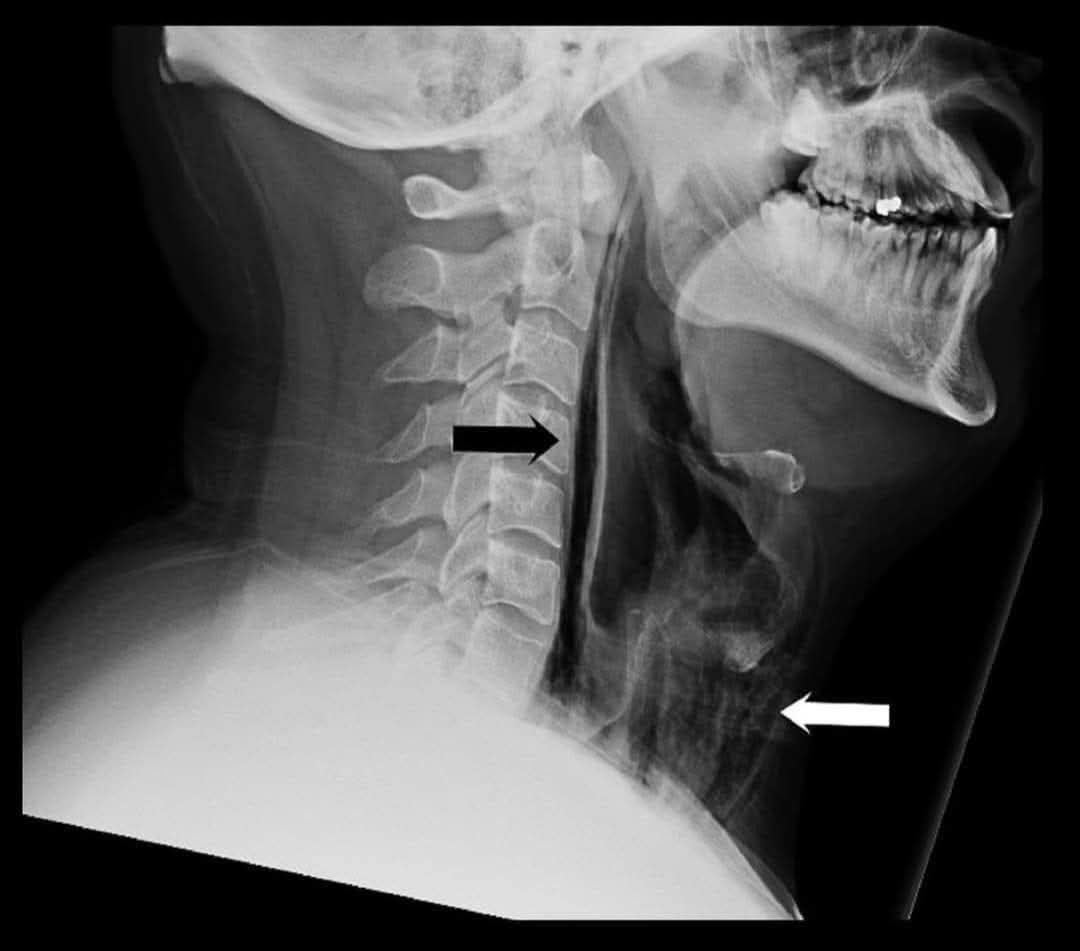

@albertoortegana @dr_manish_ydv Helluva sneeze to get air in the retropharyngeal space

🩺A 34-year-old patient, previously healthy and in good physical condition, presents to the emergency department with severe odynophagia and a change in voice after sneezing while covering both the mouth and nose at the same time.

Neck X-ray